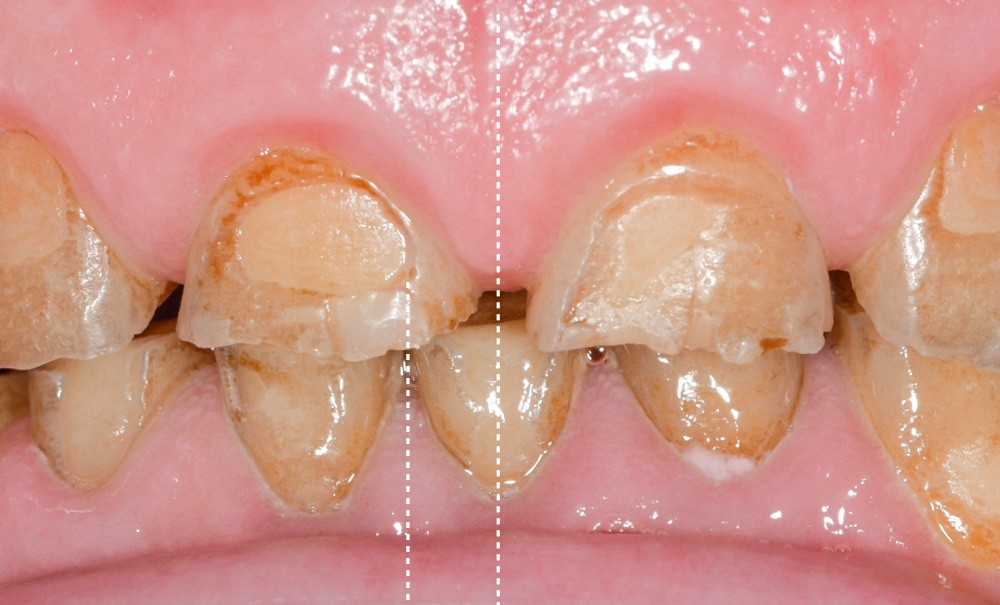

Les changements de mode de vie et les modifications de l’alimentation conduisent de plus en plus fréquemment à la prise en charge de patients présentant de larges lésions d’usure, associées éventuellement à une perte de la dimension verticale de l’étage inférieur de la face. Dans ce contexte, la santé des articulations temporo-mandibulaires, en particulier en présence de dysfonction temporo-mandibulaire (DTM), constitue un paramètre essentiel dans la conduite des étapes cliniques. L’enchaînement de ces étapes doit être mené de manière logique et chronologique afin de garantir une intégration optimale de la réhabilitation globale. Cet article, construit autour d’un cas clinique, illustre à la fois une prise de décision thérapeutique argumentée et la réalisation, à l’aide de techniques conventionnelles, des réhabilitations provisoires et définitives.